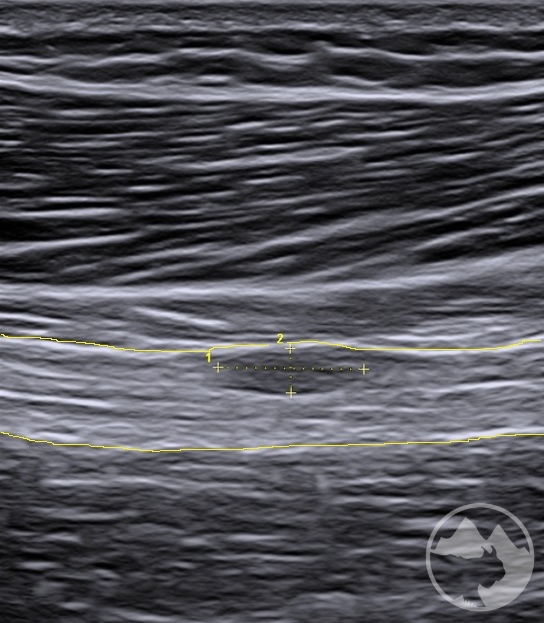

Workshop bude zaměřen nejen na samotné zobrazení daných nervů ve svém průběhu, nýbrž i na důležité topografické souvislosti s dalšími strukturami jako jsou kosti, svaly, cévy, vazy nebo fascie a na identifikaci anatomických „markerů“ a rizikových míst. V rámci několika přednášek budou zopakovány anatomické průběhy nejčastěji vyšetřovaných nervů včetně běžných variací, budou prezentovány možnosti měření, správného nastavení dopplerovského módu, ukázky úžinových syndromů a jiných patologických nálezů včetně důležitých „redflags“. Převažovat však budou praktické ukázky vyšetření a nácviky v malých skupinách. Vyšetřovací postupy zahrnou běžné statické zobrazení i skenování při pohybu, tzn. testy neurodynamiky. K dispozici na vyzkoušení budou standardní sondy i moderní vysokofrekvenční sondy s rozlišením umožňujícím hodnocení jednotlivých nervových fasciklů. Součástí přednášek ani praktických nácviků nebudou intervenční postupy.